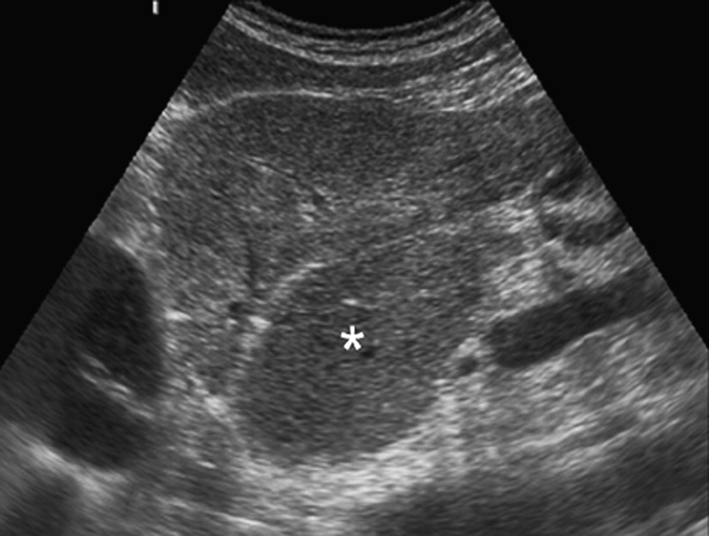

caudate lobe hypertrophy

in setting of cirrhosis the caudate lobe may be enlarged

cirrhosis

enlarged caudate lobe